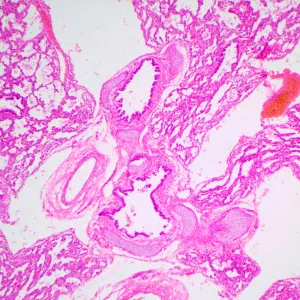

MAGUS Bio 240T – небольшой биологический микроскоп для студенческих занятий и исследований. Ориентирован на работу с прозрачными и полупрозрачными препаратами биологического происхождения в светлом поле. Микроскоп отличается наличием кодированного револьвера, который поддерживает выбранную интенсивность света для каждого объектива, и ЖК-дисплея, на котором отображаются параметры работы.

- Работает с прозрачными и полупрозрачными биологическими препаратами в светлом поле